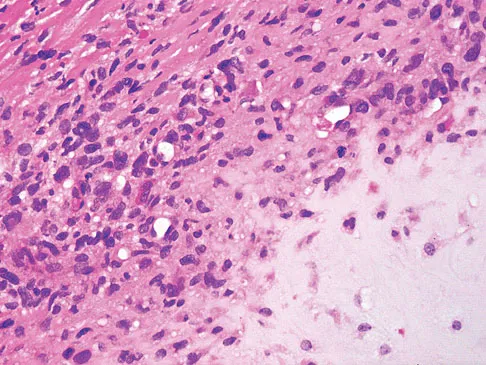

A healthy 16-year-old boy has had increasing pain in the right knee for the past 3 months. Examination reveals warmth and swelling around the distal femur. Radiographs and an MRI scan are shown in Figures 51a through 51c, and a biopsy specimen is shown in Figure 51d. What is the most likely diagnosis?

Explanation